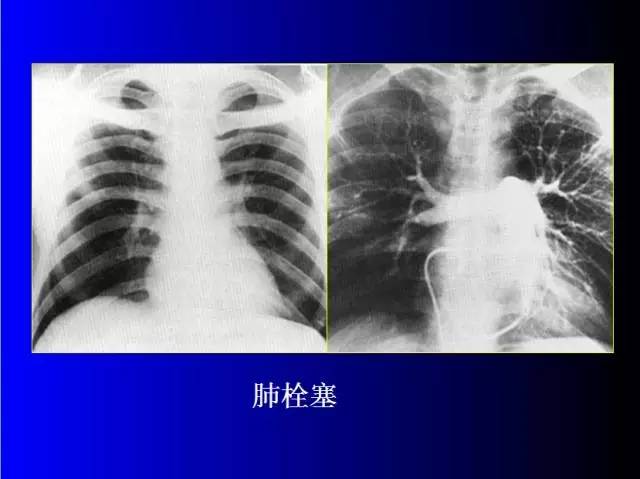

肺部基础X片及CT片解读